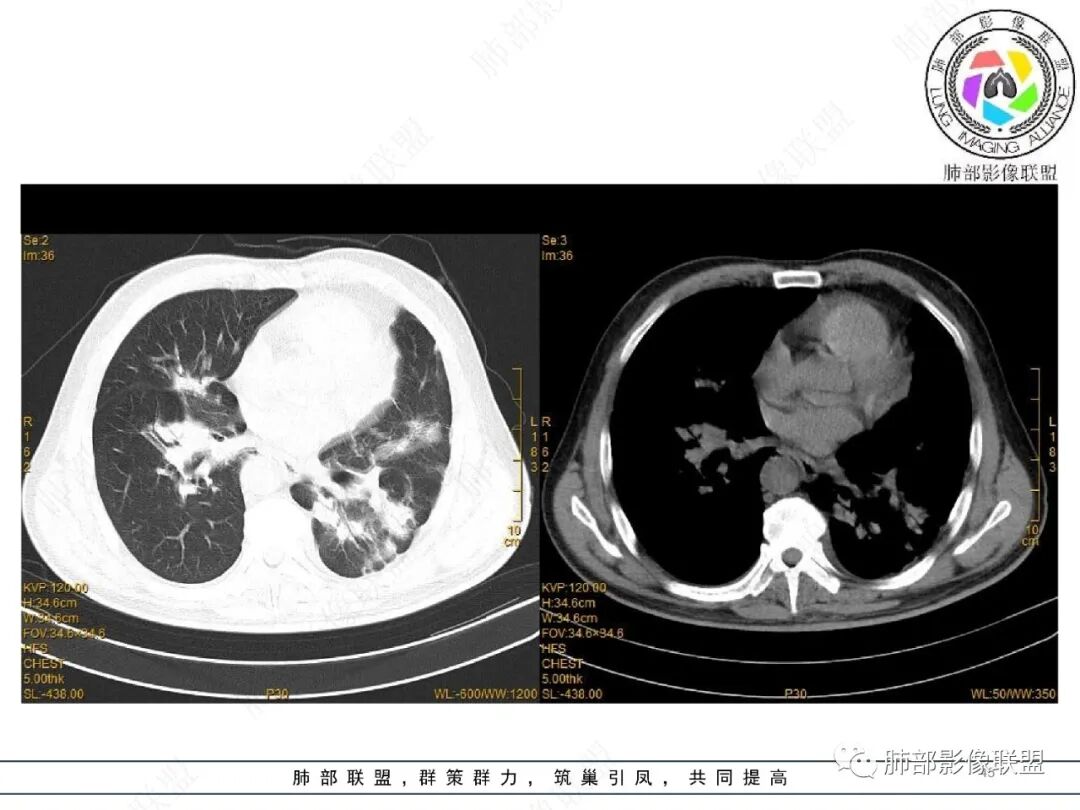

2022.2.17CT显示两肺中内带多发结节影、斑片影、条索影,部分病灶侧向融合与胸膜平行。部分病灶沿着支气管血管束分布、其内支气管稍扩张。部分病灶呈反晕征。大部分病灶边界显示清晰,部分病灶周围可见边界不清的GGO。2022.4.12CT显示两肺中内带多发结节影、条索状、条带状高密度影,边界收缩平直凹陷,大部分病灶沿着支气管血管束分布,亦有位于胸膜下侧向融合与胸膜平行的病灶。总体与第一次CT对比两肺病灶明显吸收。